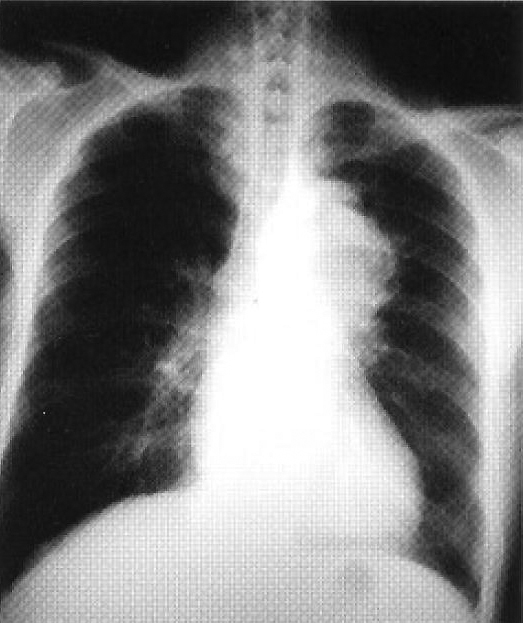

Preoperative CXR (Figure 1) was normal. Blood results revealed WBC ~10 x l09/dl; Hb 9.0 g/dl; CRP 7.05mg/dl; ESR >l40mm/hr. Liver & renal function tests, clotting profile were normal; immune markers were unremarkable. Synovial biopsy showed nonspecific synovitis; joint fluid for bacteriological studies were negative.

Figure 1: Normal preoperative CXR